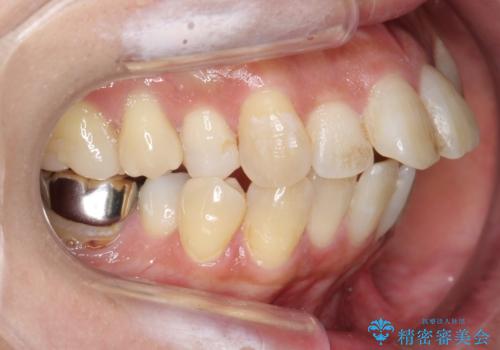

上の前歯が出ていた為、しっかり口を閉じることが難しい状態でしたが、楽に閉じられるようになりました。

側貌(横顔のライン)が治療前には下顎が後退したような状態が、口元を引っ込めたため相対的にしっかり前に出て見えるようになり、大きく改善しています。